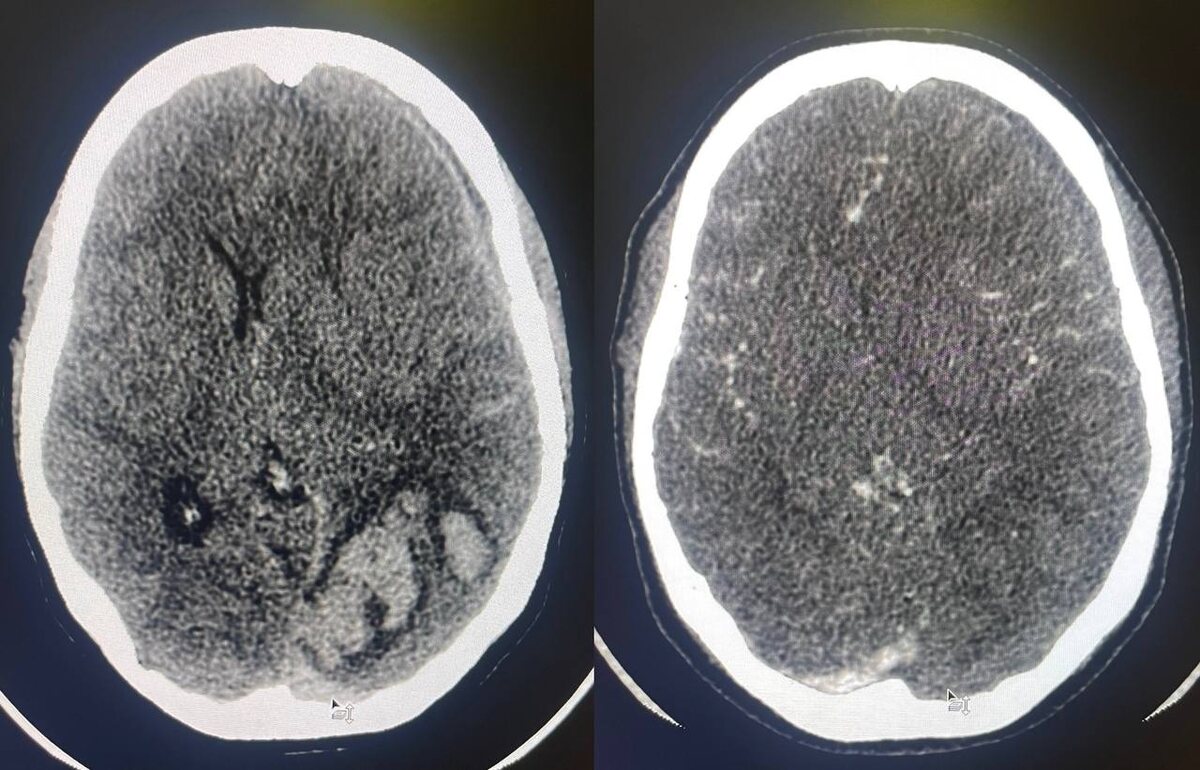

Центральный венозный тромбоз встречается реже артериального, но забывать о нём из - за этого не стоит, внимательно проверяя и венозную фазу сканирования тоже, особенно при наличии внутримозговой гематомы - которая является одним из непрямых его признаков.

На МСКТ: фрагментированная внутримозговая гематома в левой затылочной доле головного мозга. САК. ВЖК. Субдуральная гематома вдоль левого полушария головного мозга с распространением вдоль межполушарной щели и намёта мозжечка слева. Дислокация срединных структур. КТ - признаки формирующегося отёка вещества головного мозга. Дефект контрастирования поперечного, сигмовидного синусов слева и дистального отдела левой внутренней яремной вены.

Обратите внимание на фото, как светится тромбированный левый поперечный синус на нативе в сравнении с дефектом контрастирования при введении контрастного препарата. Тот же принцип, что и при окклюзии артерий. Хотя синусы и так могут быть достаточно яркими, так что признак неубедительный. А вот показательную картинку с прямыми и непрямыми КТ - признаками центрального венозного тромбоза добавлю в комментариях.